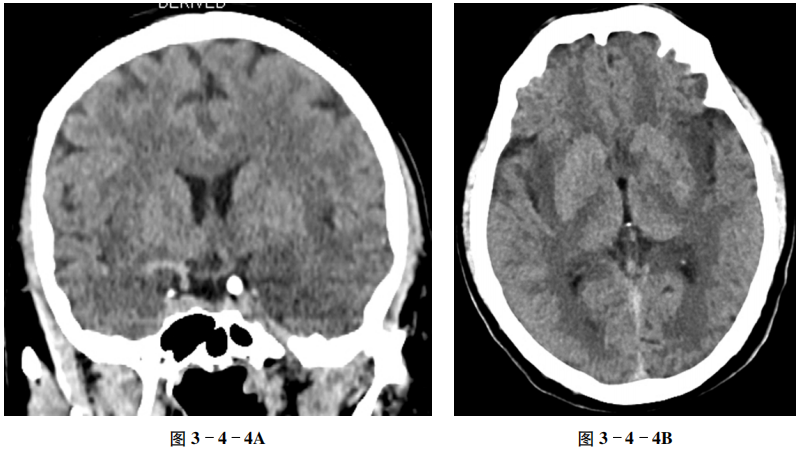

例4 病毒性脑炎

【病史摘要】 男性,46岁。发热9天,意识不清伴频繁抽搐3天。

【CT及MRI征象】 CT平扫示双侧颞叶、岛叶片状稍低密度影,边界模糊,局部脑沟变窄(图3-4-4A、B)。MRI T2-FLAIR(液体衰减反转恢复序列)显示双侧病变位于颞叶海马及岛叶,并较对称分布(图3-4-4C)。

【重要征象】 双侧边缘叶稍低密度影,刀切征(与豆状核分界清晰)。